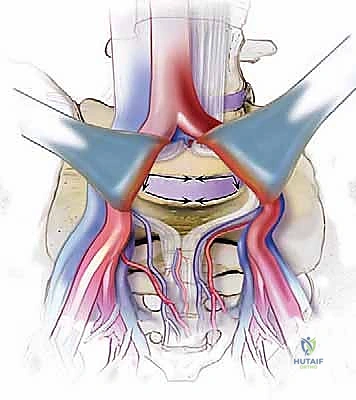

الخطوة 2: التعامل مع الأوعية الدموية (Vascular Mobilization)

هذه هي الخطوة الأكثر دقة. أمام العمود الفقري القطني توجد الأوعية الدموية الكبرى في الجسم (الشريان الأورطي والوريد الأجوف السفلي وتفرعاتهما). باستخدام أدوات دقيقة ورؤية مكبرة، يتم تحريك هذه الأوعية بلطف شديد لحمايتها وكشف القرص الفقري المستهدف (غالباً L4-L5 أو L5-S1).